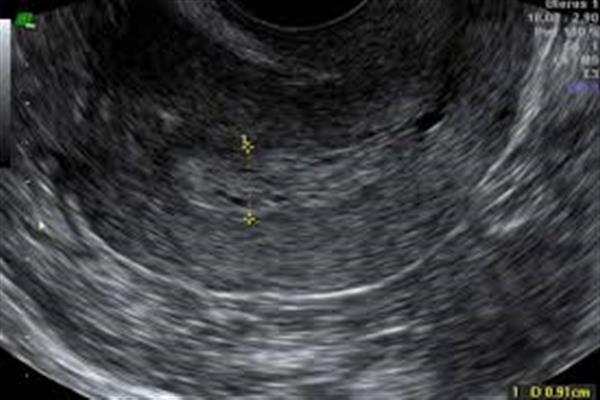

روشهای انجام سونوگرافی اوایل بارداری

سونوگرافی ترانسواژینال: این روش تصویری دقیقتر از رحم و جنین در هفتههای اولیه ارائه میدهد. برای این کار، پروب سونوگرافی درون واژن قرار میگیرد و به پزشک امکان میدهد که جزئیات بیشتری از رحم و جنین مشاهده کند.